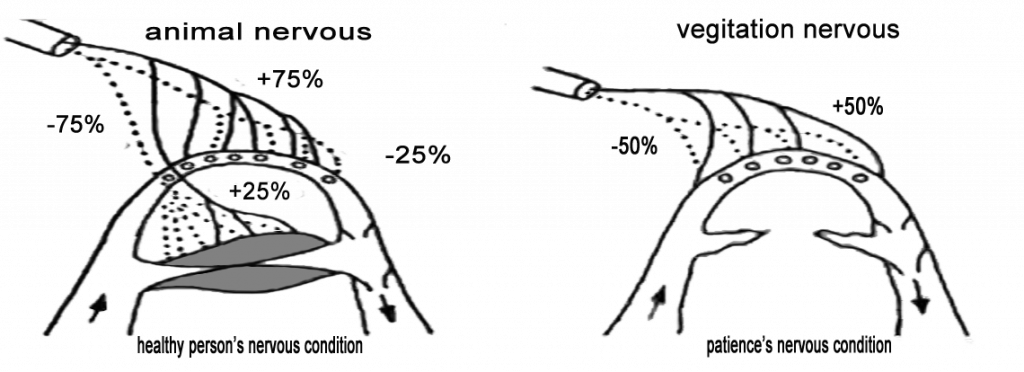

Glomus “The Glomus becomes paralyzed when blood clots obstruct the blood vessels. If this condition persists, the person is going to die. This new natural medicine treatment: GRF Medicine Restores your cell vitality and improves the quality of life. The usual wear and tear of our primary organs (kidney, stomach, liver, lung, heart). During the average lifetime of seven decades, our body grows old, and the average life of 80 to 85% of capillaries is damaged. We have 40 billion capillaries throughout our body (100,000 miles). “Glomus is the gateway to the blood, oxygen, nutrients and waste/sludge removal. Glomus is the bodies emergency response system that is triggered during life threatening incidents. “Glomus is the gateway to our body’s system of supplying blood, oxygen, and nutrients.

When this natural circulatory system has problems, the blood stops and loses its place to go any further. Finally, people will die. A pale complexion when shocked and frightened causes a rapid contraction of the capillaries. This is because the blood is temporarily blocked.

Red blood cells, white blood cells, platelets, and other types of ingredient’s flow in a row single file. At this time, impurities in the blood (pigment, uric acid, thrombus & blood) cannot flow and capillaries If the tube is blocked, the glomus will become functionally disrupted within a few weeks. Cell tissues under these capillaries are more likely to stop nutrient supply and the problem is that hemoglobin in the red blood cells cannot supply oxygen, so the cells cause complications in proper functioning of body immune systems, leading to serious diseases including cancer.